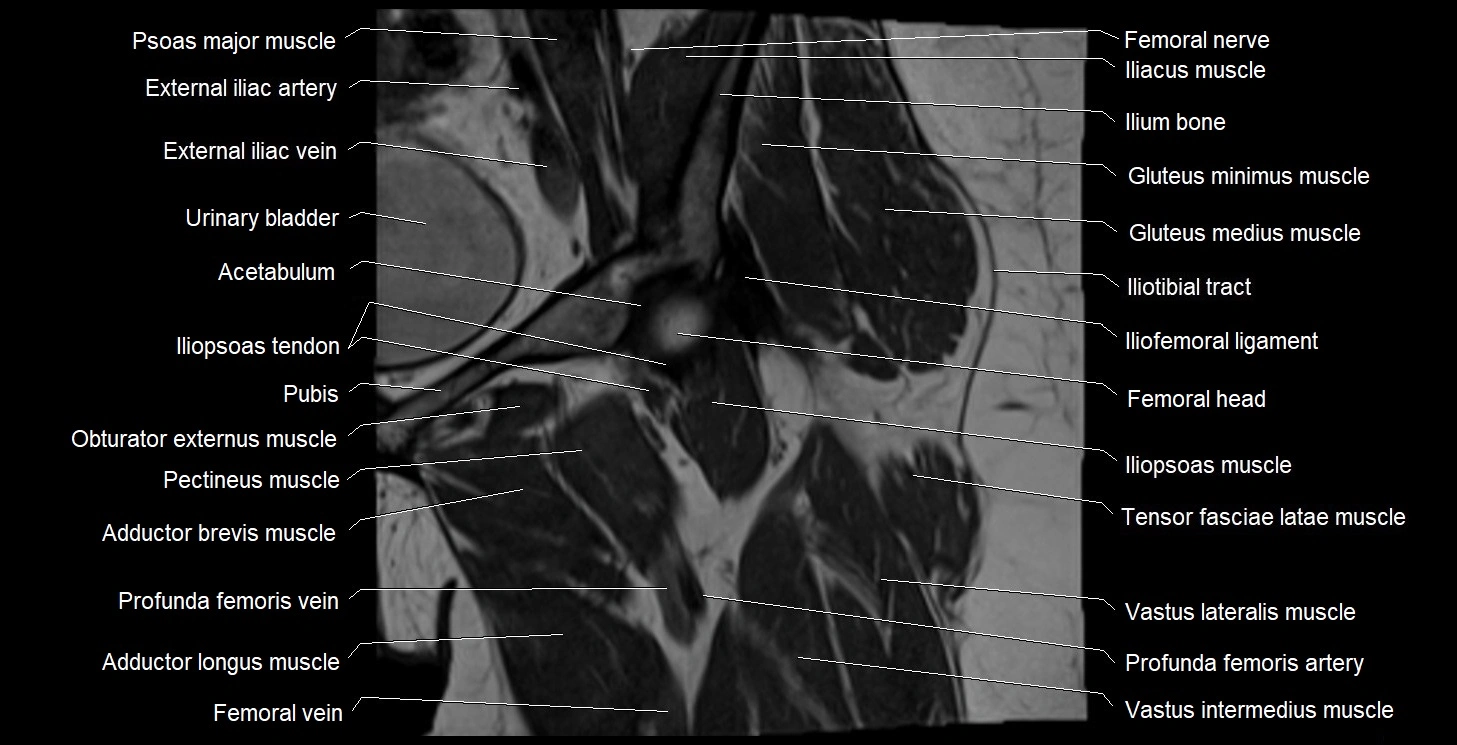

- Acetabulum

- Adductor brevis muscle

- Adductor longus muscle

- Deep femoral vein (profunda femoris vein)

- External iliac artery

- External iliac vein

- Femoral nerve

- Femoral vein

- Femur

- Head of femur

- Iliofemoral ligament

- Iliopsoas muscle

- Iliopsoas tendon

- Iliotibial tract

- Ilium bone

- Obturator externus muscle

- Pectineus muscle

- Psoas major muscle

- Tensor fasciae latae muscle

- Urinary bladder

- Vastus intermedius muscle

- Vastus lateralis muscle

- Vastus medialis muscle